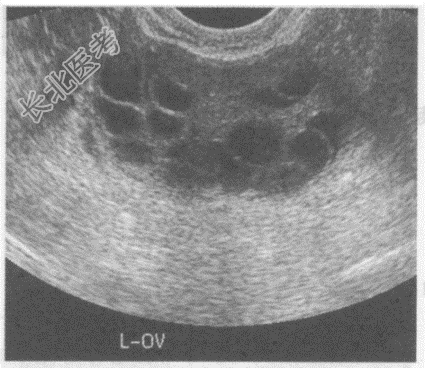

- 单项选择题临床资料:女性患者, 29岁,自述自幼肥胖, 多毛,月经稀少, 结婚5年不孕。

化验检查:雄激素与睾酮升高。

超声综合描述: 经阴道扫查,子宫小, 内膜显示不清;双侧卵巢均匀性增大。包膜光滑增厚回声增强, 每个超声切面可见>10个大小不等无回声区,最大直径0.9cm, 透声清亮。

B、多囊卵巢综合征